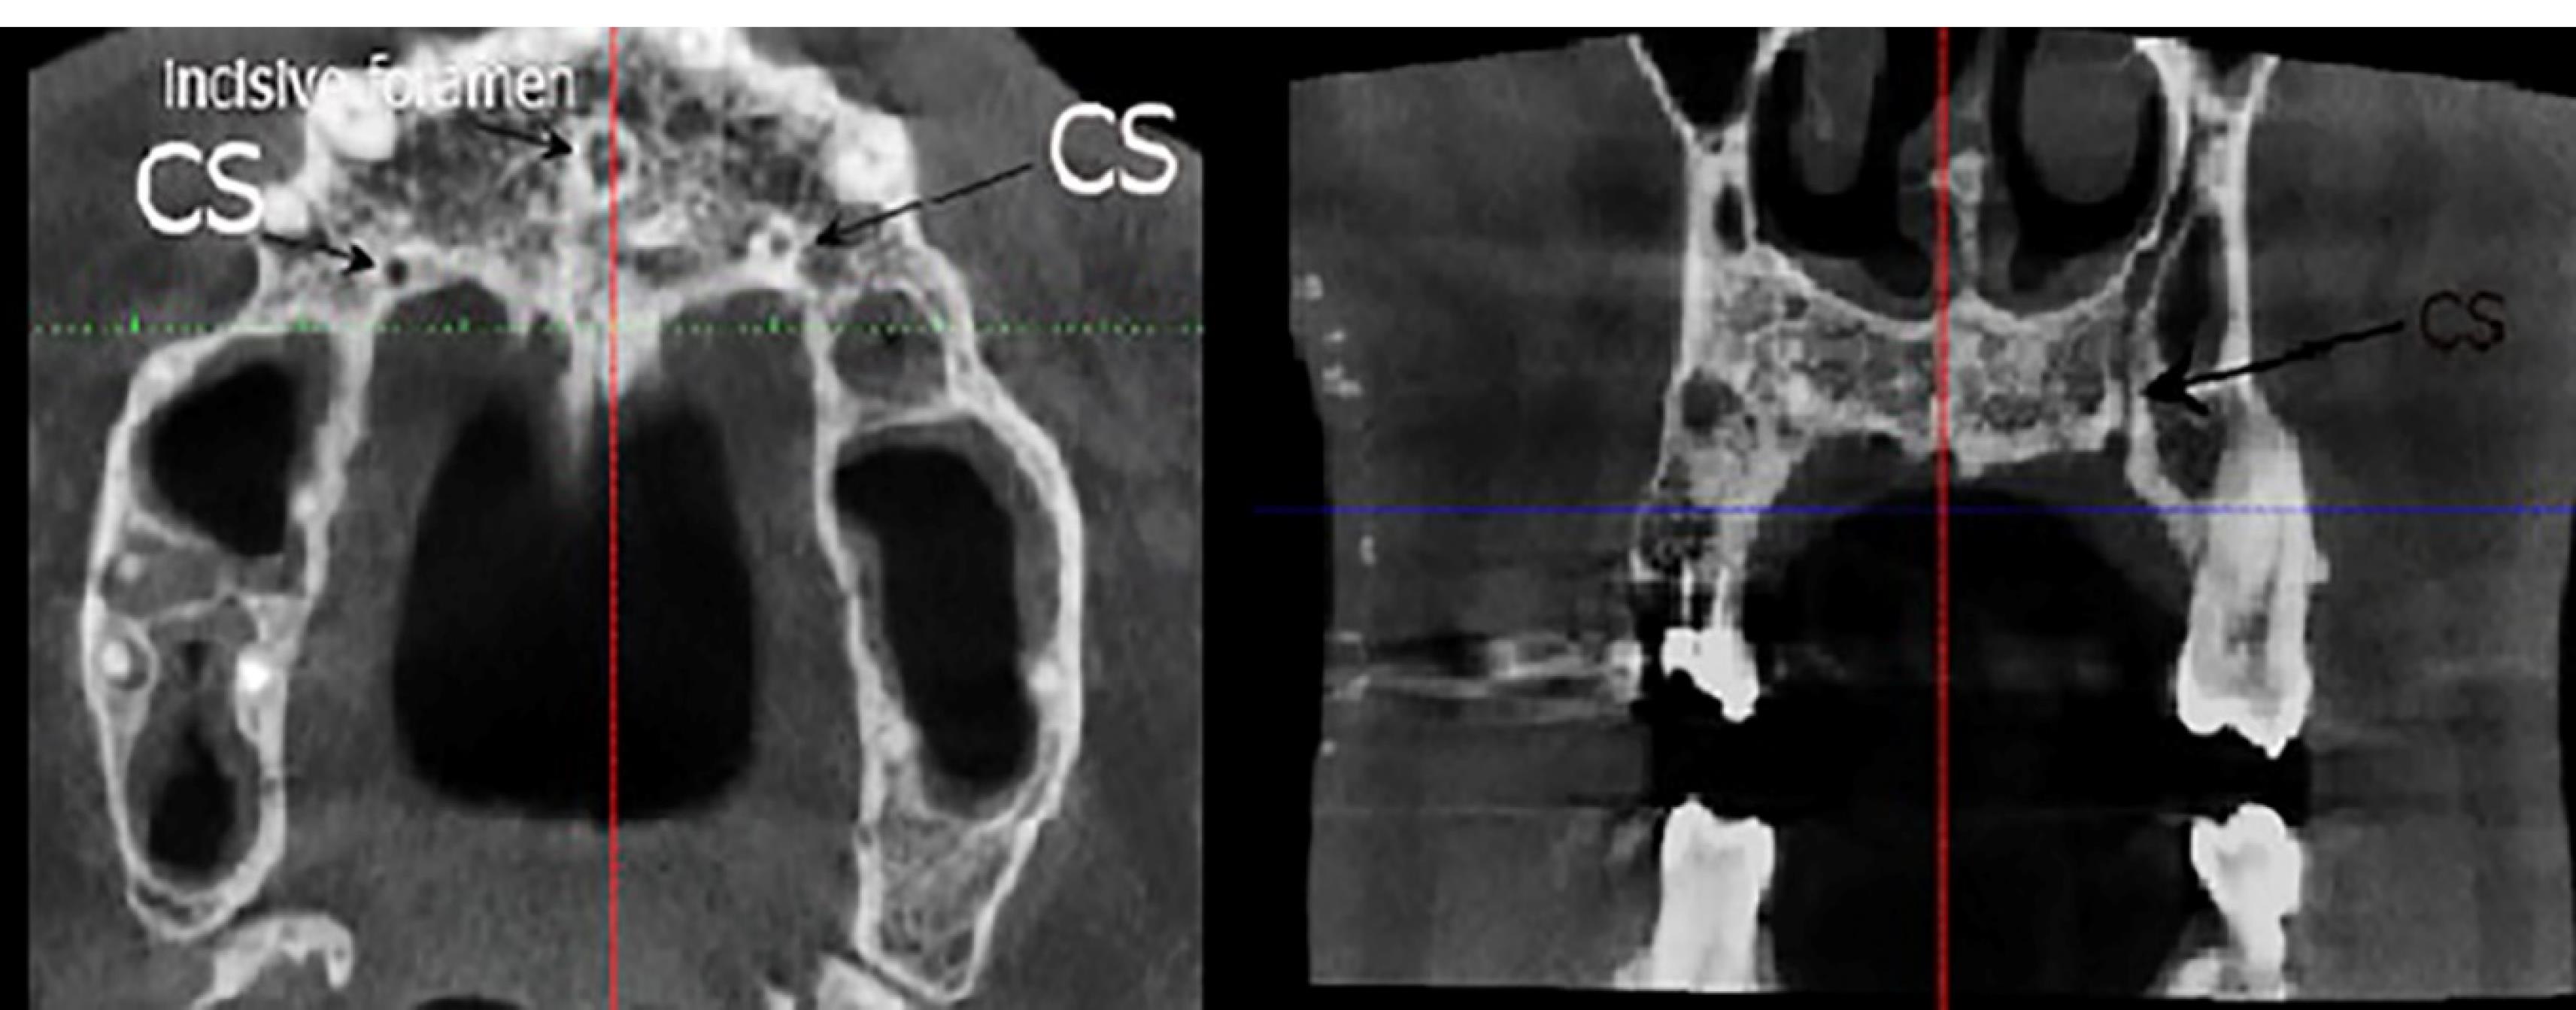

Figure 3.

Linear measurements made in the cross-section: D, the CS distance from the crest ridge; E, the CS distance from the nasal cavity floor; F, the CS distance from the buccal cortical plate; G, the distance of canal extension from the main tooth apex